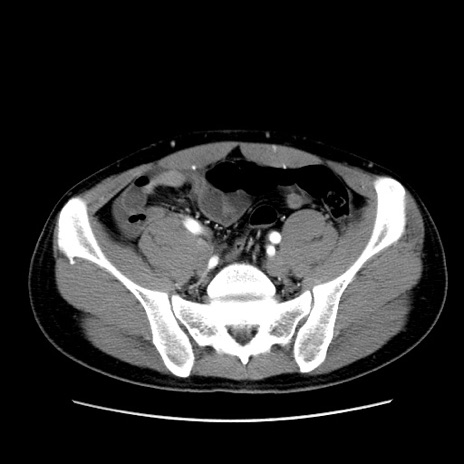

症例36(横断像)

【症例】20歳代 男性

【主訴】心窩部痛

【現病歴】今朝より上腹部痛あり。一旦軽快していたが再度出現したため救急要請。昨日夕に白身の魚を含む刺身を食べた。

【身体所見】BP 136/89mmHg、HR 74/min、BT 37.0℃、腹部:膨満、軟、心窩部に圧痛あり。反跳痛なし、筋性防御なし、腸雑音やや亢進あり。

【データ】WBC 17700、CRP 0.48